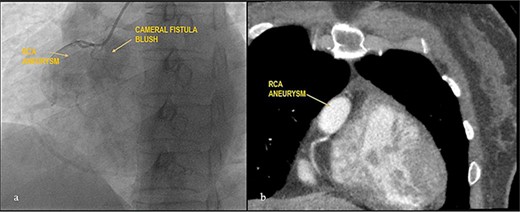

Apparently healthy 44-year-female being evaluated as a potential donor for renal transplant, her echocardiography showed dilated right atrium and ventricle with moderate tricuspid regurgitation. Gated cardiac CT was done which revealed proximal RCA aneurysm measuring 2.1×2.4 cm and CAG which revealed RCA–right atrial (RA) cameral fistula. Heart arrested with antegrade cardioplegia after aorto-bicaval cannulation. RA fistula suture ligated through right atriotomy. The aneurysm excised, RCA mobilized and reimplanted into right sinus of valsalva (RSOV). On weaning off of bypass, severe RV dysfunction observed and cardiopulmonary bypass re-initiated. RCA bypass with reverse saphenous vein graft (RSVG) was done. Figures 2 and 3 show radiological and intraoperative images. She had a stormy postoperative course with multiple episodes of ventricular arrhythmias probably attributed to sacrifice of the infundibular and nodal branch, but was eventually discharged on 11th day after surgery.

Giant RCA aneurysm with CCF. (a) CAG showing RCA aneurysm with RA blush; (b) RCA aneurysm in cardiac CT.